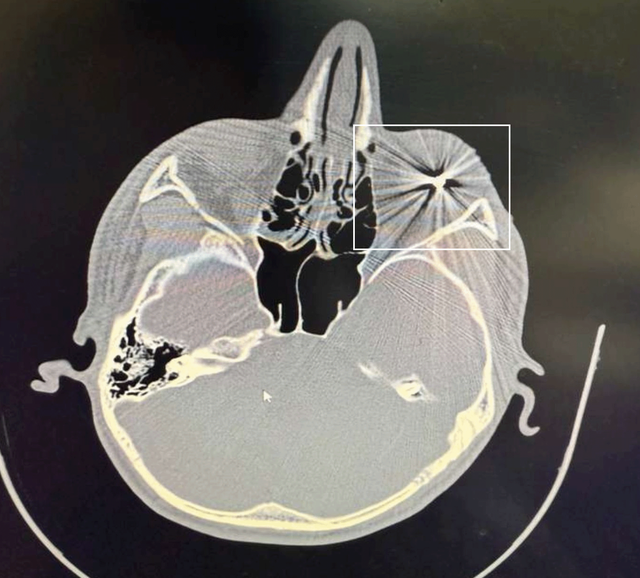

Dhe BBC News Persian ka siguruar skanime CT dhe të dhëna mjekësore të disa protestuesve të plagosur nga Mashhadi, njëra prej të cilave tregon qartë një fishek metalik të ngulitur në indin e syrit.